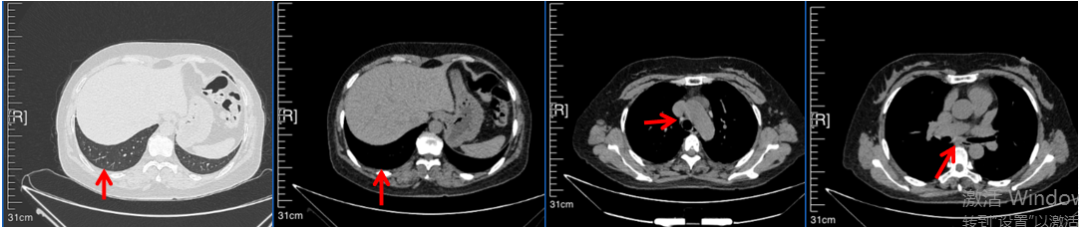

治疗经过:2023年3月27日始行恩沙替尼靶向治疗至今,最佳疗效为PR,末次评效为维持PR。期间出现轻度肝功能异常(DILI 1级),对症处理后好转。截止目前PFS为26个月。

2024年6月复查PR(最佳疗效)

2024年12月复查维持PR

2025年3月复查维持PR